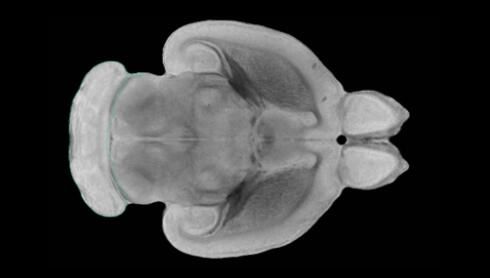

隨著機體年齡增加,肌肉和關節(jié)都會變得僵硬,這就會使得日常活動變得更加困難,本文研究表明,我們的大腦也是如此,與年齡相關的大腦僵硬對大腦干細胞的功能或許有著重要影響。文章中,研究人員對年輕和老化大鼠的大腦進行研究闡明了年齡相關大腦僵硬對少突膠質(zhì)前體細胞(OPCs,oligodendrocyte progenitor cells)功能的影響。OPCs是一類對維持正常大腦功能非常重要的大腦干細胞,其對于髓磷脂的再生也非常重要,髓磷脂是神經(jīng)組織周圍的脂肪鞘,在多發(fā)性硬化癥中髓磷脂的再生常常會被損傷,機體老化對這些細胞的影響常常會誘發(fā)多發(fā)性硬化癥的發(fā)生,這些細胞的功能在老化的健康人群中同樣會下降。

為了確定老化OPCs的功能缺失是否可以被逆轉,研究人員將來自老化大鼠機體的老化OPCs轉移到了年輕大鼠柔軟的海綿狀大腦組織中去,值得注意的是,這些老化的大腦細胞能夠重新恢復活力,其行為非常像年輕更加強壯的細胞。這項研究中,研究人員在實驗室中開發(fā)出了具有可變僵硬程度的新型材料,并在受控環(huán)境下研究這些材料的生長及其對大鼠大腦干細胞的影響,這些材料能被工程化改造具有和年齡或老化大腦相似的柔軟程度。

為了深入理解大腦組織柔軟和僵硬影響細胞行為的分子機制,研究人員對細胞表面一種名為Piezo1的蛋白質(zhì)進行了分析,該蛋白質(zhì)能“告知”細胞其周圍的環(huán)境為柔軟或僵硬。研究者Kevin Chalut說道,我們發(fā)現(xiàn),當在僵硬材料上促進年輕具有功能性的大鼠干細胞時,這些細胞就會表現(xiàn)出功能異常,并失去其再生的能力,實際上其行為與老化細胞相似。當將老化的大腦細胞在柔軟材料上生長時,其功能就會表現(xiàn)得像年輕細胞一樣,換句話說,其能夠重新恢復年輕的活力。